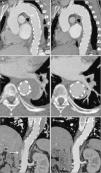

CTA one month after hospital discharge showed intimal rupture of one of the aortic ulcers and evolution to localized dissection, with a pseudoaneurysm of the proximal segment of the descending aorta measuring 27 mm×51 mm (Figure 3). In the light of these findings, the patient was rehospitalized and after discussion with the interventional cardiologist and cardiothoracic surgeon, it was decided to perform thoracic endovascular aneurysm repair (TEVAR). Two endoprostheses (Valiant® 38 mm×150 mm and 34 mm×150 mm) were implanted, the proximal prosthesis adjacent to the emergence of the left subclavian artery without obstructing its flow, and the distal prosthesis extending down to the beginning of the abdominal aorta, thus covering the ulcers, the pseudoaneurysm, the patent ductus arteriosus and most of the IMH. Post-procedural CTA confirmed that the TEVAR had been successful but an image consistent with dissection was observed in the abdominal aorta distally to the distal endoprosthesis, from the celiac trunk to the superior mesenteric artery, both of which emerged from the true lumen, as did the renal arteries (Figure 4A–C). It was not possible to confirm whether this dissection had been present prior to the TEVAR procedure, since the previous CTA had limited acquisition of the thoracic region. It was decided to adopt a conservative approach to this finding.

CTA 30 days after discharge, showing evolution of the hematoma to dissection and a pseudoaneurysm measuring 27 mm×51 mm in diameter with a 23-mm neck (A, B and C). The pseudoaneurysm was located in the mid segment of the descending aorta, and intimal rupture originated in the aortic wall ulcer that had shown signs of progression on the second exam; three-dimensional volume reconstruction following thoracic endovascular aneurysm repair, showing two overlapping endoprostheses, from the left subclavian artery to the beginning of the abdominal aorta (D).